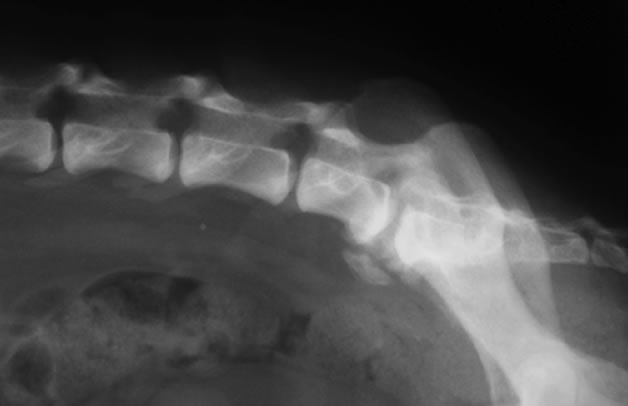

脊椎骨折、脱臼

症状:腰背部の痛み、前肢と後肢もしくは後肢の歩様失調や麻痺

頸椎、胸椎、腰椎、仙椎の骨折や脱臼。多くは交通事故や高所からの落下などの外傷にともなって起こります。診断にはレントゲン検査、脊髄造影検査、CT検査、MRI検査などが必要です。骨折や脱臼が生じた部位や重症度によって手術方法は変わります。